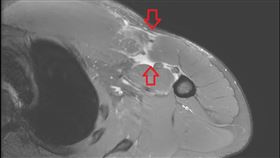

他健身突胸痛腫脹 竟罕見「胸大肌斷裂」

近年台灣健身風潮盛行,但健身也得小心隱藏傷害。一名2...